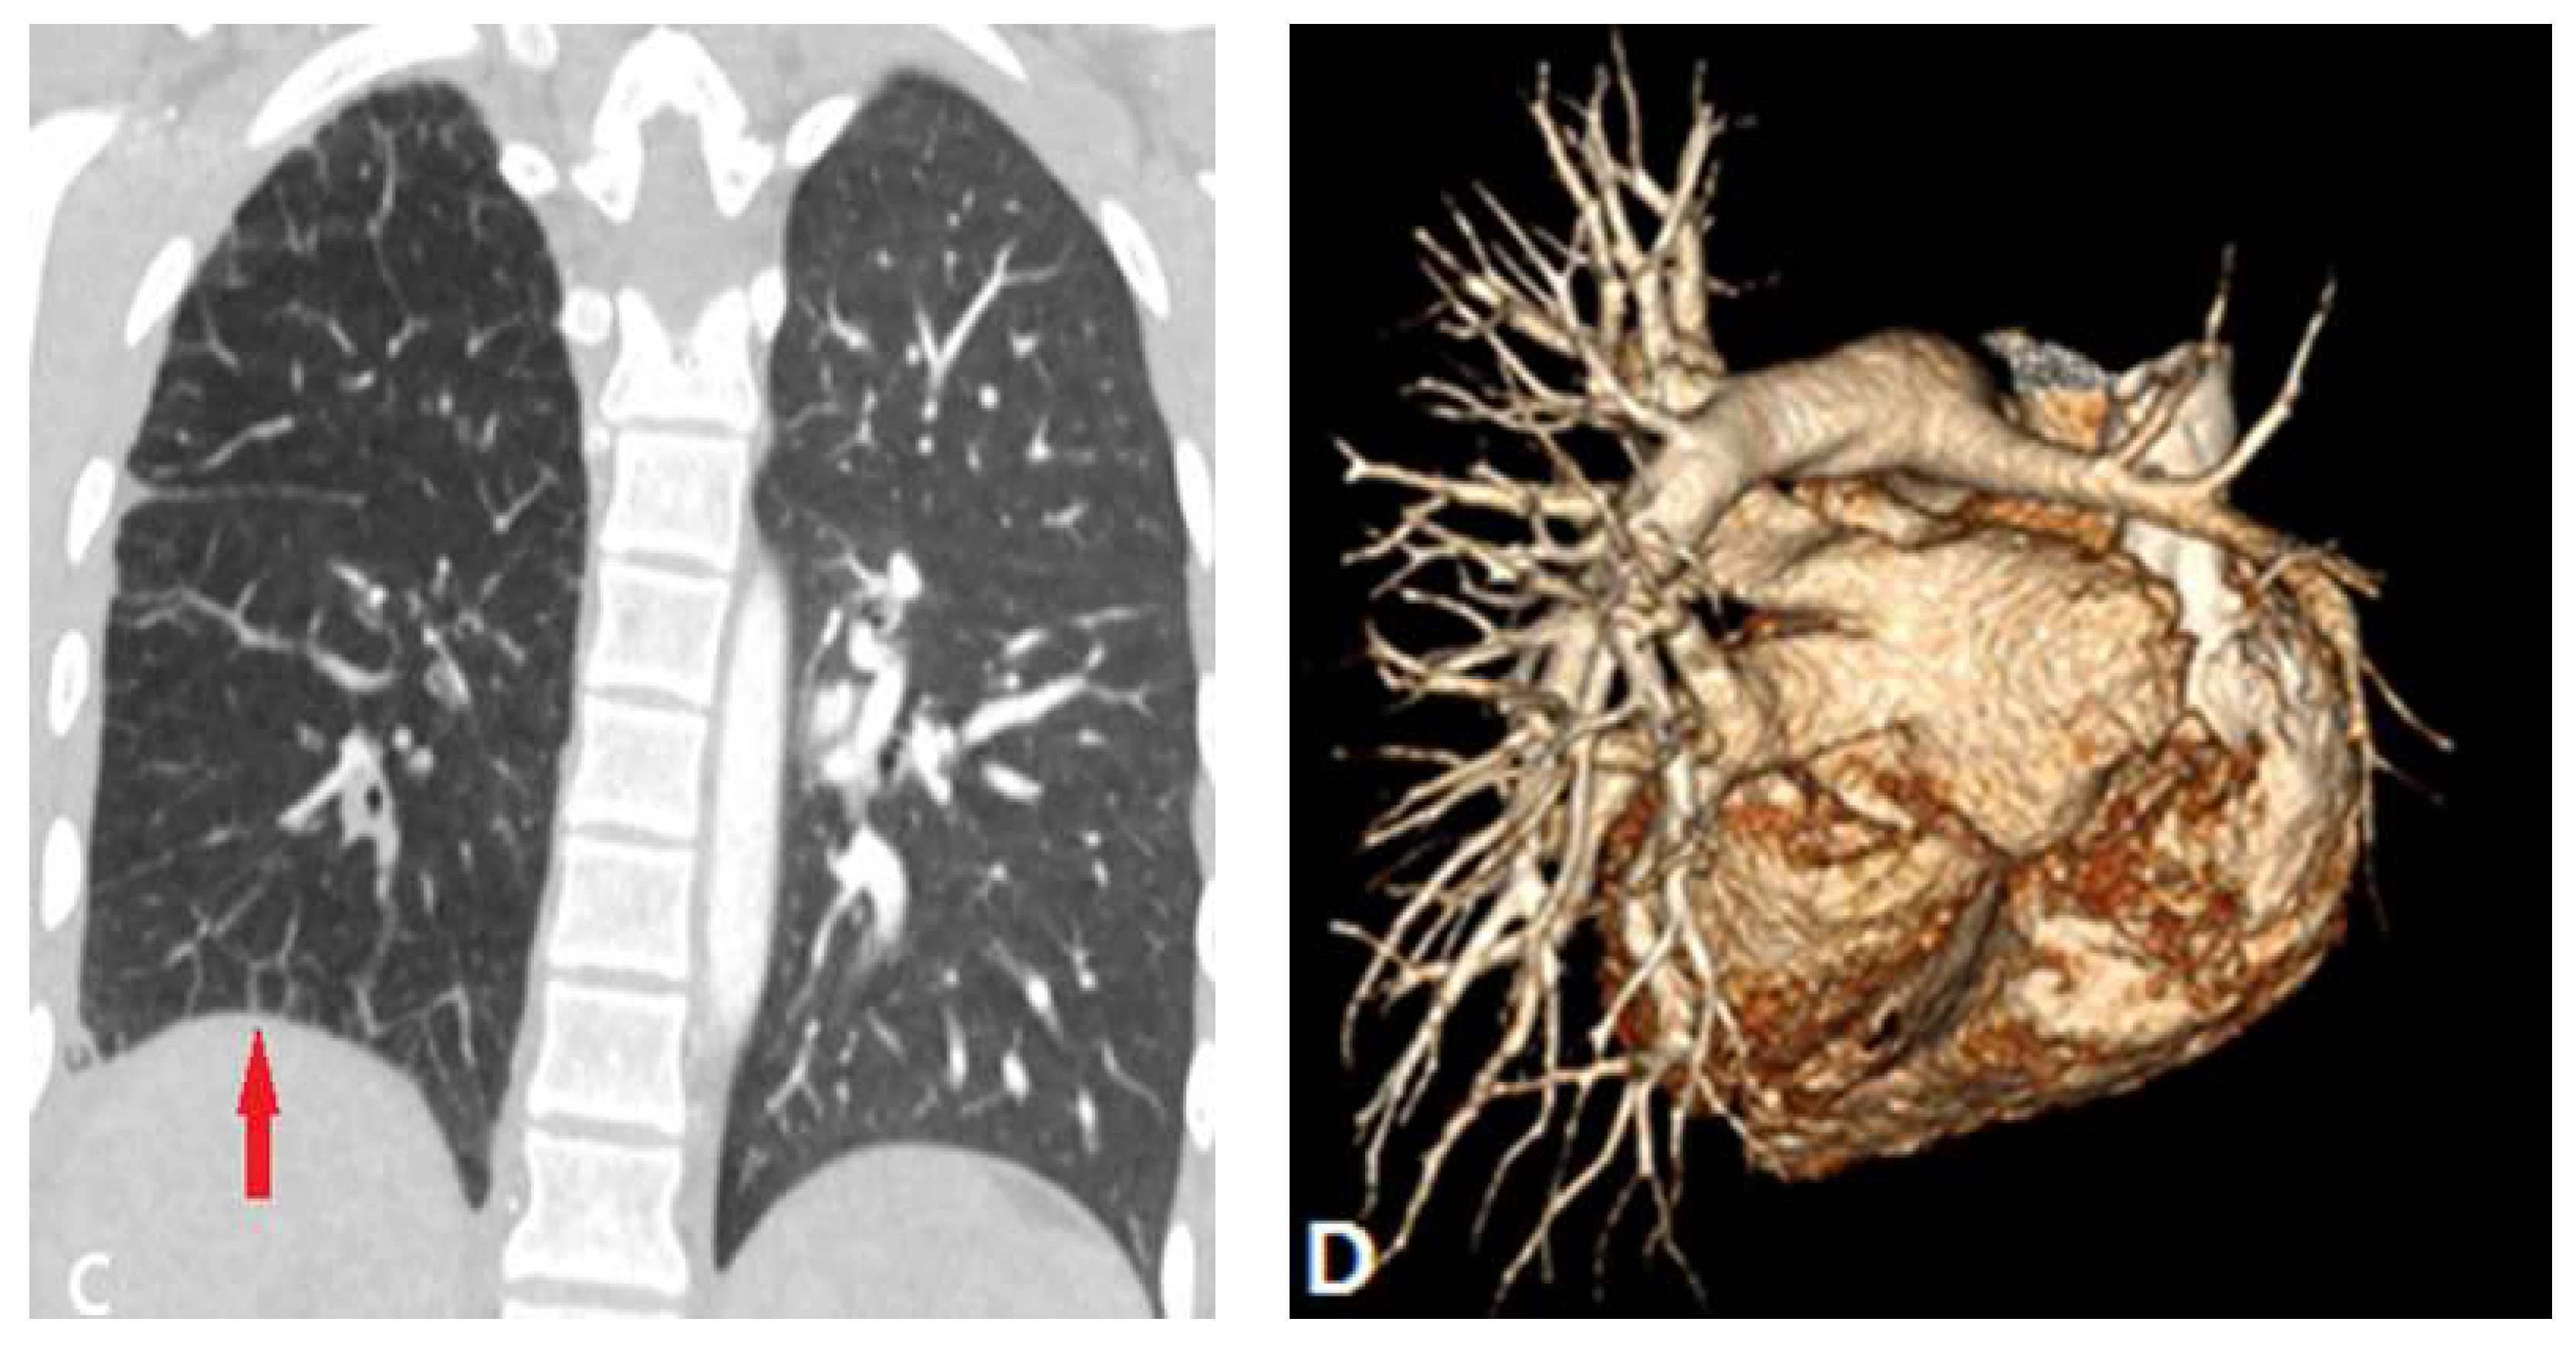

4. Complications of Radiofrequency Ablation Of Atrial Fibrillation

- Alfudhili, K.M.; Hassan, H.H.; Abdullah, H.; Sherbiny, M. Pulmonary vein occlusion and lung infarction complicating non-treated moderate single pulmonary vein stenosis after radiofrequency ablation of atrial fibrillation. BJR|. Case. Rep. 2017, 18, 20160091. [CrossRef]

- Xu, L.; Cui, L.; Hou, J.; Wang, J.; Chen, B.; Xue, X.; Yang, Y.; Wu, J.; Chen, J. Clinical characteristics of patients with atrial fibrillation suffering from pulmonary vein stenosis after radiofrequency ablation. J. Int. Med. Res. 2020; 48(3), 0300060519881555. [CrossRef]

- Ravenel, J.G.; McAdams, H.P. Pulmonary venous infarction after radiofrequency ablation for atrial fibrillation. AJR. Am. J. Roentgenol. 2002, 178(3), 664-6. [CrossRef]